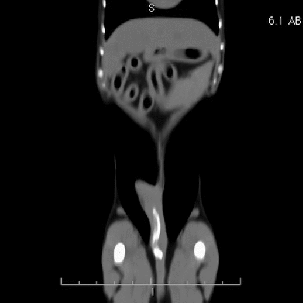

Comme la majorité d’entres vous le recommandiez, nous avons échographié l’abdomen de ce chien sans toutefois arriver à identifier le corps étranger (flèche jaune). Il faut toutefois préciser que l’estomac était légèrement dilaté par de l’air, tout comme le côlon transverse qui le longe tout juste caudalement. Il n’y avait pas de signe de perforation (air libre ou épanchement liquidien). Cependant, les gras étaient hyperéchogènes tout près du caecum qui se trouvait sous l’arche costale du côté droit. En raison de la minceur du corps étranger et pour éviter une longue chirurgie exploratrice possiblement non fructueuse, une tomodensitométrie (CT-scan) a été proposée pour en déterminer la localisation. Sur les images reformatées en différents plans (voir ci-bas), le corps étranger a été localisé dans les gras tout juste derrière le corps de l’estomac. Fait intéressant, il n’y avait pas d’air libre dans la cavité péritonéale. Ces informations ont permis au chirurgien de rapidement identifier le petit fil de métal en palpant doucement les gras derrière l’estomac. Le petit corps étranger n’était pas visible à l’oeil nu et aurait probablement été difficile à trouver sans l’aide du CT. On spécule que le petit fil de métal provenait d’une brosse à BBQ. Comme quoi il faut savoir brosser avec modération !